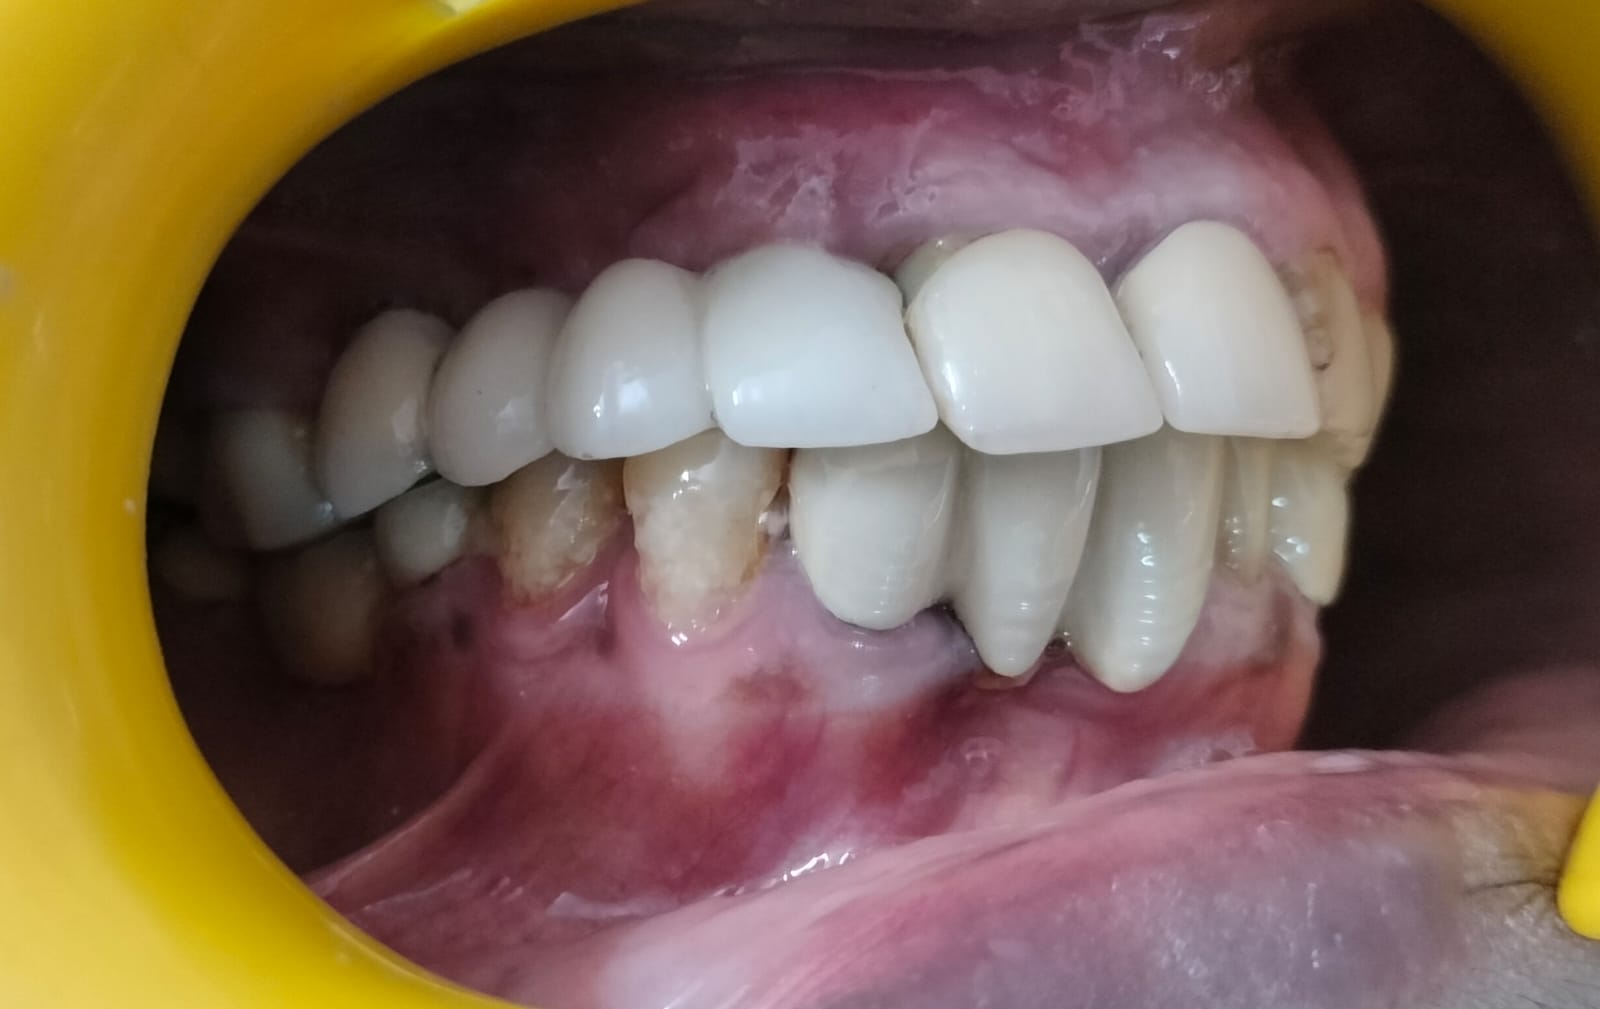

Missing teeth can affect your smile, confidence, and ability to chew properly. Fortunately, modern dentistry offers a reliable and long-lasting solution—dental implants. If you are searching online for a “Dentist near me” or the “Best dental implant clinic in Noida,” you can find world-class dental implant treatment at Dental Lifecare in Sector 71, Noida. With advanced technology, strict sterilization protocols, and personalized care, this clinic has become one of the most trusted centers for implant dentistry.

At Dental Lifecare in Sector 71, Noida, patients receive high-quality treatment from experienced specialists who focus on restoring both function and aesthetics. Whether you are missing a single tooth, multiple teeth, or even all teeth, dental implants can provide a permanent and natural-looking solution.

When choosing a clinic for dental implants, experience and expertise play a crucial role. Dental Lifecare in Sector 71, Noida is widely recognized as the best dental clinic in Noida for advanced implant dentistry.

As a skilled Implantologist in Noida, Dr. Gupta has successfully treated thousands of patients with missing teeth. His expertise in prosthodontics and implant dentistry allows him to restore both function and aesthetics with precision.